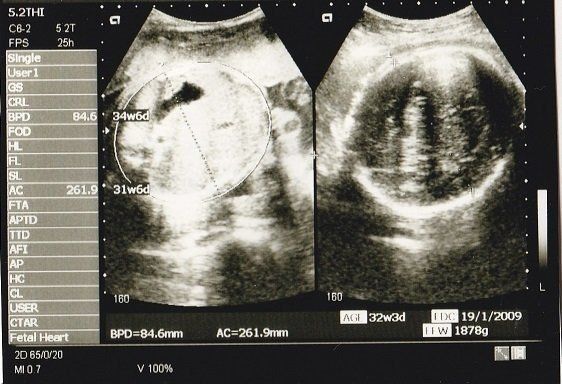

ちゃじゅびさんの妊娠32週目のエコー写真 おなかもぱんぱんです。

AC(おなかの周囲の長さ)などから、赤ちゃんの推定体重を計算するようです。赤ちゃんのおなかも大きくなっていますが、お母さんのおなかもぱんぱんです。